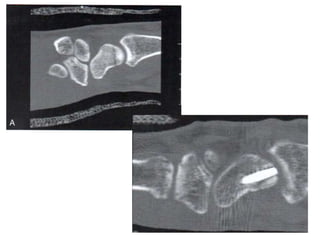

4. Estudios Radiográficos

• 4 proyecciones: AP, L, 2

Oblicuas

• Rx AP: Empuñadura de la

mano con dedos

flexionados

– Plano mas paralelo a la

placa

– Acentúa separación con

semilunar

• Rx AP con

desviación cubital:

Perfil completo de

cintura

• Rx L: alineación y

estabilidad del carpo